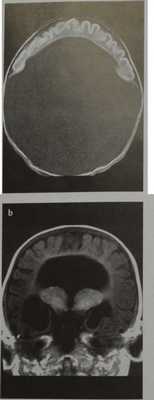

Алобарная голопрозэнцефалия:

- Слияние таламусов

- Отсутствуют третий желудочек, продольная щель, серп большого мозга и мозолистое тело

- Большой мозг припаян к ростральному отделу полости черепа

- Один большой желудочек, сообщающийся с большой задней кистой

- Возможно также слияние орбит

- Непарная передняя мозговая артерия.

Лобарная голопрозэнцефалия:

- КТ мало информативна

- Гипоплазия лобных рогов боковых желудочков б Наличие задней половины мозолистого тела

- Наличие продольной щели и серпа большого мозга, которые доходят до лобного отдела головного мозга

- Иногда встречается гипоплазия переднего отдела серпа большого мозга.